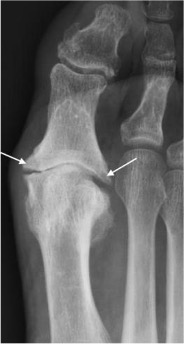

Osteoarthritis

- Narrowing and irregularity of joint space

- Subarticular sclerosis with subchondral cysts Osteophytes

- Bone density usually maintained

- In late stages, the joint becomes partially or fully ankylosed and osteophytes may fracture, causing loose intra-articular bodies

Osteoarthritis of the 1st MTP joint with joint space narrowing, subarticular sclerosis and marginal osteophytes (arrows)